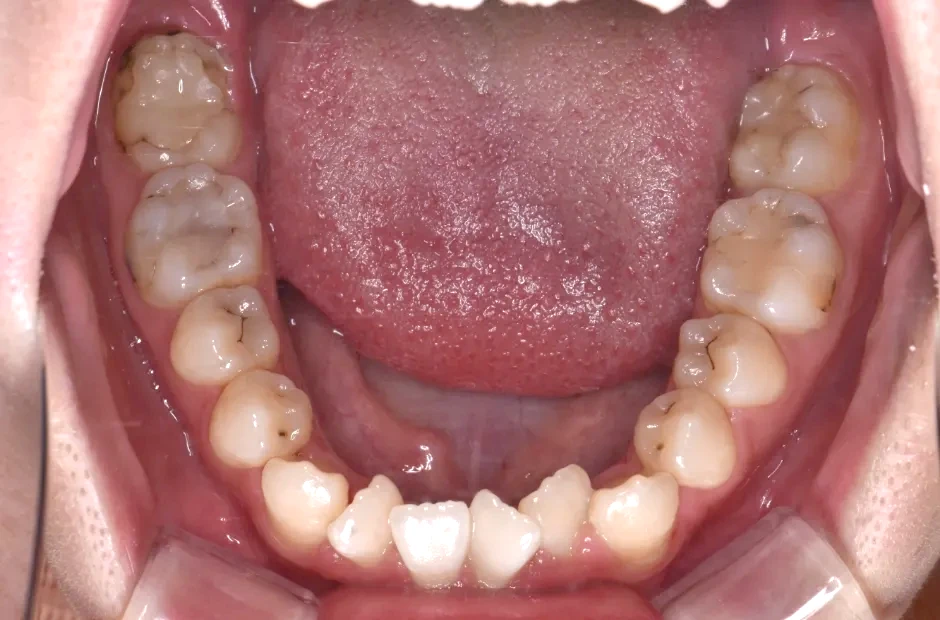

叢生

| 診断名・主訴 | 叢生 |

|---|---|

| 年齢・性別 | 43歳・女性 |

| 治療期間・回数 | 2年7か月 27回 |

| 治療に用いた主な装置 | 舌側矯正 |

| 抜歯部位 | 両顎4,4 |

| 治療費 | 100万円(税抜) |

| リスク・副作用 | 装置による違和感・疼痛・歯肉退縮・歯根吸収・虫歯のリスクなど |

治療前

治療中

治療後